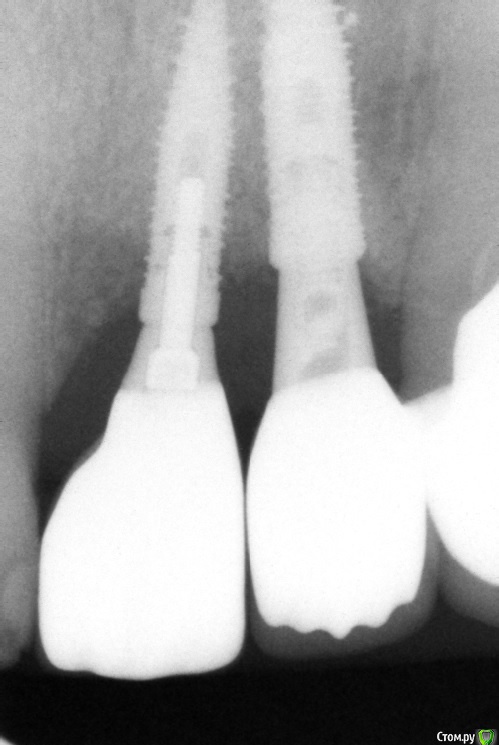

Irouil Опубликовано 11 августа, 2018 Поделиться Опубликовано 11 августа, 2018 Работа не моя В 2015 установленный 2.2, в 2016 - 2.1. зондируется около 5 мм вестибулярно от 2.1, около 7 между ними, около 3-4 у 2.2. оголился абатмент 2.2. Насколько адекватно будет тащить это на мягких тканях? Хочу с бугра в сосок и вестибулярно с неба. Ссылка на комментарий

колесников Опубликовано 11 августа, 2018 Поделиться Опубликовано 11 августа, 2018 Я бы если и взялся с десной работать,то только с заменой абатмент на 22ом. Мягким тканям нужна поддержка,с такого абатмент все улетит снова. Если нет возможности изменить форму абатмента,какой нибудь из имплантолов заглушил и предложил консоль. Правда на такой вариант, ни один из имплантов не внушают доверия. 1 Ссылка на комментарий

колесников Опубликовано 13 августа, 2018 Поделиться Опубликовано 13 августа, 2018 Когда кости нет ,вы проводите деснев аугментацию ,о которой сейчас речь,зачем? Очевидно чтобы компенсировать дефицит объема и создать каркас для маргинальной слизистой. Мягкие ткани не растут вертикально,Лоскуту самому нужна поддержка ,чтобы сохранять первоначальную форму. Этой поддержкой может быть корень зуба или костные пики, ни того ни другого в данном случае нет. За что будет держаться лоскут,как питаться,как форму сохранять? Очевидно что он осядет. Дайте ему дополнительные «зацепы» в гладких и вертикальных стенках абатмента. Ссылка на комментарий